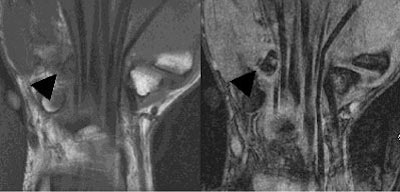

T2-weighted images with fat suppression are also very helpful in demonstrating the bone marrow and soft-tissue edema that is associated with an acute fracture. Coronal images, often obtained in MR imaging of the wrist, are limited in their ability to display most fractures of the hook of the hamate, due to the coronal orientation of most of these fractures.

| Coronal MR images illustrate the difficulty in visualizing fractures of the hook of the hamate. These fractures (black arrows) are in the coronal plane, and are therefore difficult to visualize on both the T1-weighted (right) and gradient echo (left) images. Images courtesy of Dr. Douglas P. Beall. |